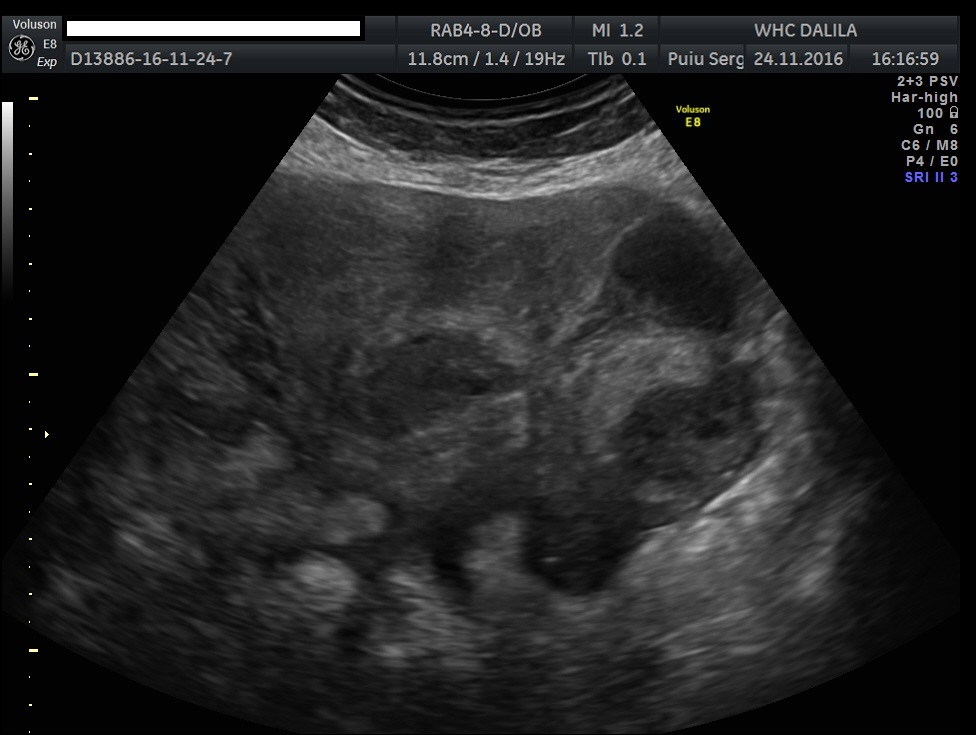

Transvaginal and transabdominal ultrasound scans were performed, which has shown the enlarged uterus with indistinct borders on the left side and a complex mass in left lower abdominal quadrant. A large irregular thick-walled, ill-defined multiloculated cystic/solid lesion with complex fluid collections and peripheral flow on color Doppler were seen. The anatomic distinction between the ovary and the fallopian tube could no longer be identified (Fig. 1). A tubo-ovarian abscess (TOA) was presumed. Endovaginal sonogram showed a dilated uterine cavity and cervical canal, filled with heterogeneous, complex fluid and echogenic masses (Fig. 2a-c). An intrauterine contraceptive was detected. A cavity within myometrium with low-level internal echoes fluid also was revealed (Fig. 2c). This complex adnexal mass was adherent to uterus and a communication between TOA and the cavity within myometrium with fluid-debris level fluid was detected (Fig. 3a-b). This finding presumed a perforation of the TOA into uterus, due to myometrium necrosis, and spontaneous drainages into uterine cavity through myometrium. Increased echogenicity of the pelvic fat and a small amount of free fluid in cul-de sac also were seen. Fluid movements through fistula canal between TOA and uterine cavity were clearly seen when a gently pressure by ultrasound probe was applied (Video 1).

Figures 3a-b. Transvaginal and transabdominal ultrasound scans. A complex adnexal mass adheres to uterus and a communication (fistula) between TOA and a cavity within myometrium and then into endometrial cavity with low level echoes fluid is clearly seen. Increased echogenicity of the pelvic fat and a small amount of free fluid in cul-de sac also can be seen.